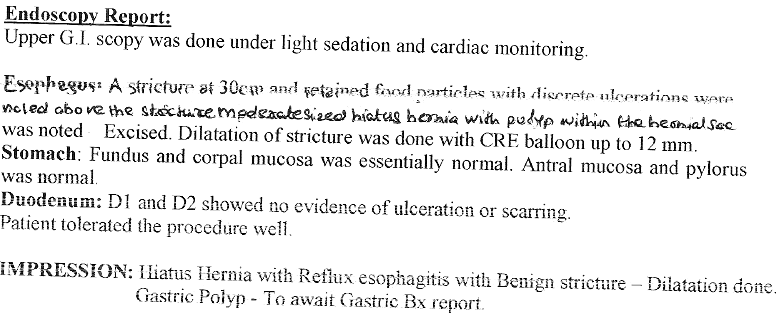

4. Diagnosis of Hiatus Hernia

5. Vomiting of blood / coffee coloured fluid is a serious symptom which may be due to ulcers, cancer of upper GI tract or due to cirrhosis of liver. These conditions can be accurately diagnosed by gastroscopy and majority of these conditions can be treated by endoscopy without need of surgery.

Vomiting of Blood - Endoscopic Treatment

5. Vomiting of blood can be due to severe acidity, consumption of pain killers or blood thinners, ulcer, cancer, cirrhosis of liver etc..

Correct diagnosis and treatment can be offered to these patients.